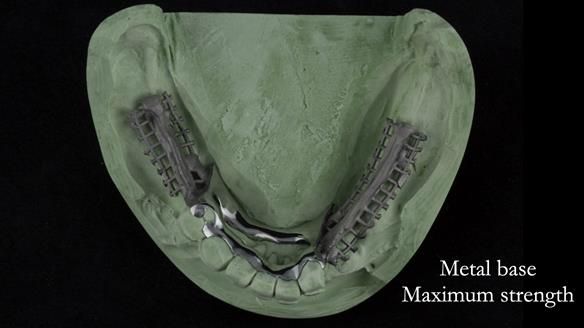

Instead, we made a Scandinavian-style, metal-based lower RPD.

It’s worth saying that the lower denture in this case was made in the early days of Rowan and me using the Scandinavian approach. Rowan cast the metalwork himself for this denture.

Looking back, we would make this denture more hygienic now. The design and finish would be more refined and delicate, particularly when compared with the upper metalwork, which was made later using Chris Hesketh’s chrome work. I will discuss this in detail at the study club.

That said, the lower denture worked beautifully. It did exactly what it was meant to do, even though, by today’s standards, it looks a little agricultural.